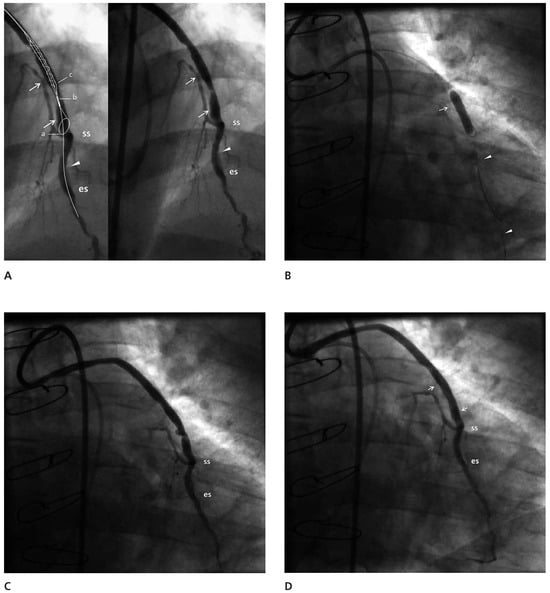

He presented with a NSTEMI with ST segment depression in the lateral leads and small elevation of myocardial enzymes (CK-MB: 48 U/l). Two weeks after his presentation a left ventriculogram demonstrated hypokinesis of the inferior wall and anterior basilar segment and a global ejection fraction of 40%. Coronary arteriography demonstrated severe diffuse stenoses of the left main, intermediate branch and circumflex artery (probably the culprit site, based on the location of the ECG changes) with complete occlusion of the distal circumflex and occlusion of the right coronary artery. The left anterior descending artery was occluded and was diffusely diseased. The only vein graft that was patent was sequentially anastomosed to the mid and distal segments of the left anterior descending artery (LAD), separated by an occluded intervening part. The vein graft borders were smooth but there was a bulky eccentric 70% stenosis close to the side to side anastomosis (Figure 1A).

Angioplasty of the distal segment of the LAD followed by angioplasty of the vein graft was performed with a JR4 8F guiding catheter. The angioplasty of the distal LAD was performed successfully and then a FilterWire™ 3.5–5.5 (FilterWire™ EZ System, Boston Scientific Corp) was deployed parallel to the guidewire that extended to the distal LAD, with the FilterWire™ loop proximal to the first of the distal anastomoses. A Sprinter 4/20 balloon (Medtronic, Inc.) was advanced on the guidewire, with its distal tip close to the FilterWire™ loop, closer than it would have been possible if it had been advanced on the FilterWire™ itself (Figure 1B). It was inflated to 18 atm with the intention to disrupt the plaque and get the maximum amount of debris collected during the “protection” phase. The FilterWire™ was properly closed and removed with the guidewire remaining in place. The vein graft plaque was obviously disrupted but the flow remained good (Figure 1C). In the filter there were two solid whitish pieces of the vein graft wall, one large and one small. (Figure 2). A stent Endeavor® Resolute 4/18 (Medronic, Inc.) with a stent balloon/reference artery diameter ratio 1:1, was advanced over the guidewire and deployed at the site of the disrupted plaque at 10 atm. Despite the presence of a small (10–20%) compression of the stent, no further dilatation was performed (Figure 1D). The flow to the LAD through the graft was good with no evidence of branch occlusion or diminished flow.

In our case, we strongly believed that we needed to use an embolic protection device because of the large area perfused by the retrogradely filled LAD. It is noteworthy that despite the data supporting the use of embolic protection devices, an analysis from the American College of Cardiology (ACC)-National Cardiovascular Data Registry, which included a total of 19 546 SVG PCI from January 2004 through March 2006, showed that embolic protection devices were used in just 22% of patients, a trend that is observed in recent trials [7]. The location of the lesion was close enough to the anastomosis for effective protection of the proximal limb of the vessel with a distal protection device. In the case of the FilterWire™, there is a structural limit to how close the tip of the balloon can get to the lower part of the wire loop and this is 12 mm. The distance of the edge of the stent to the tip of the balloon is 7 mm and so the minimum distance for effective protection for the Endeavor® stent deployment is more than 19 mm (Figure 1A and Figure 2) (personal measurements).

Figure 1. (A) The vein graft side to side (ss) and end to side (es) anastomoses are marked. The left anterior descending artery is occluded between the two anastomoses (arrowhead) and the distal part is significantly diseased. The vein graft shows a smooth border with the main stenosis, extending between the two arrows. It is obvious that the landing zone is not long enough for the FilterWire™ to provide protection for the proximal part of the left anterior descending artery. This is demonstrated in an inset, in which a cartoon superimposed on the duplicate angiogram demonstrates the positioning of the loop for the achievement of complete emboli protection and the closest distance the stent can be deployed to the loop of the FilterWire™ (ab+bc >19 mm). (B) The balloon on a parallel wire (arrowheads) is inflated covering the whole lesion close to the nitilol loop of the device. The arrow points to proximal shoulder of the lesion. (C) The result of the large balloon inflation was the disruption of the plaque. (D) The post stent implantation result is good with no evidence of protruding atheromatous material and no dissection. The edges of the stent are marked with arrows.